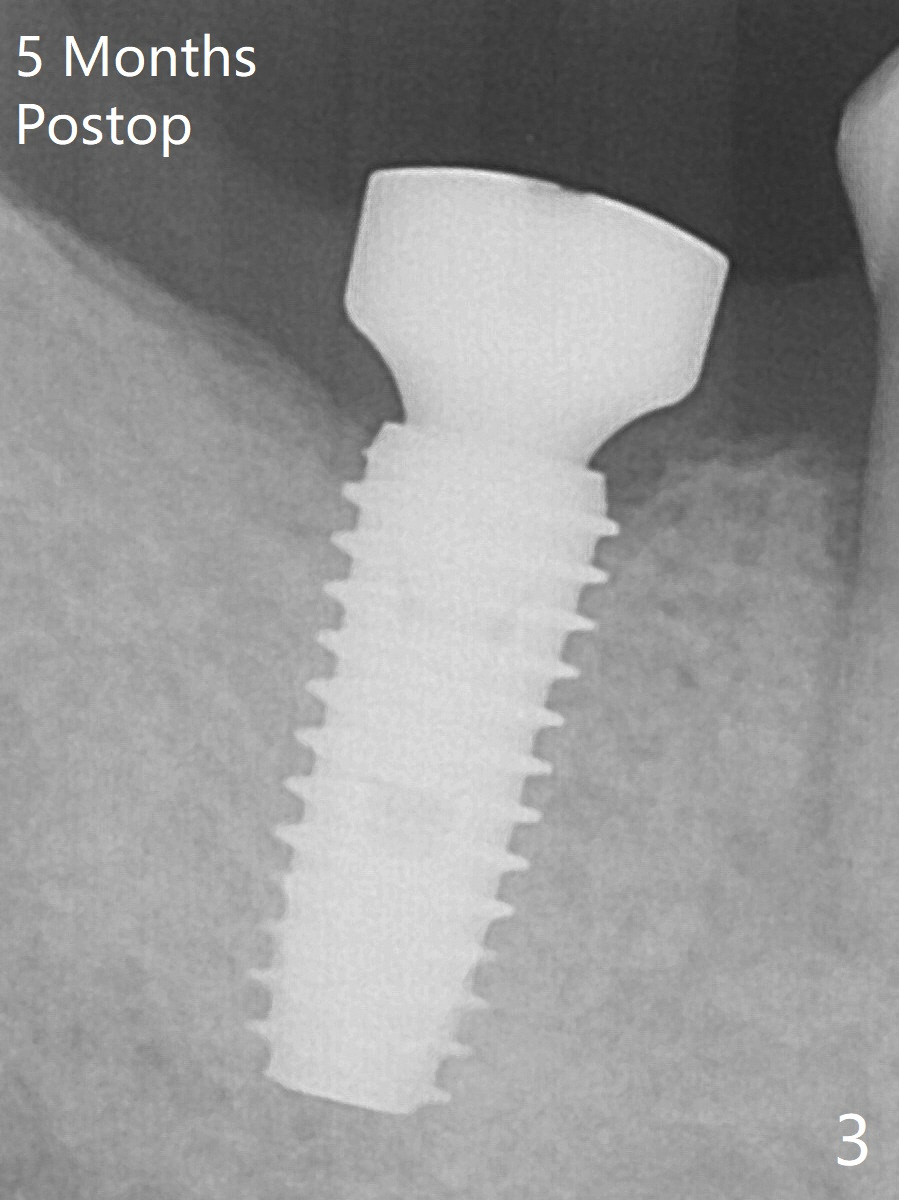

The leukoplakia at the sites of #31 and 32 is most likely related to smoking and the supraerupted teeth #1 and 2 (Fig.0 ^). After osteotomy for 11.5 mm at #31 (Fig.1), it appears that the bone height is not as much as expected. The last two drills for sequential osteotomy are 4.3x13 and 4.8x11.5 mm. A 5x11.5 mm UF implant is placed slightly subcrestal with insertion torque > 50 Ncm (Fig.2). Following placement of 6.5x2 mm healing abutment, the opposing tooth needs adjustment for height. Orthodontic intrusion of the opposing tooth is scheduled 2 days later. It is accidental to find root fracture of the mesial root of the tooth #30 (Fig.1 <). There is minimal bone resorption coronally 5 months postop (Fig.3). A provisional is fabricated at #31 to assist in intrusion of the tooth #2. A crown is cemented 11.5 months postop (Fig.4); the leukoplakia at #31 seems to lessen. The tooth #30 is lost during the pandemic, followed by looseness of the crown and abutment at #31. When the complex is reseated, the occlusal scheme is changed, suggesting incomplete seat of the abutment earlier (Fig.5).